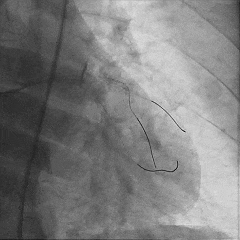

双侧造影,观察闭塞起始位置、长度、走行等

尝试通过RCA-圆锥支侧枝逆向开通LAD :

微导管辅助下,用SUOH03导丝尝试送入侧枝

经微导管TIP injection可见侧枝重度迂曲

侧枝重度迂曲,反复尝试未能通过